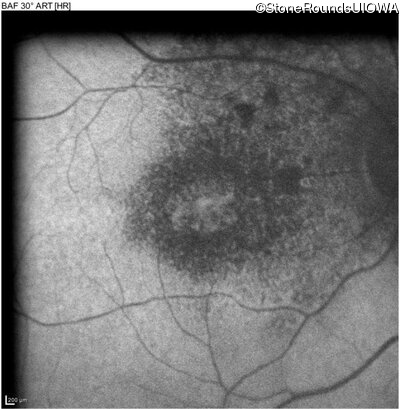

Cone-Rod Dystrophy (IA1b)

Age at visit: 58 years

This 58 year old woman first noticed a gap in the vision of her left eye at age 46.

Diagnosis & molecular findings

Disease Gene Allele 1 variant(s) Allele 2 variant(s) Inheritance mode

Cone-Rod Dystrophy CRB1 Cys948Tyr (T)GT>(T)AT Asp165 del9cagGATGGAATT AR